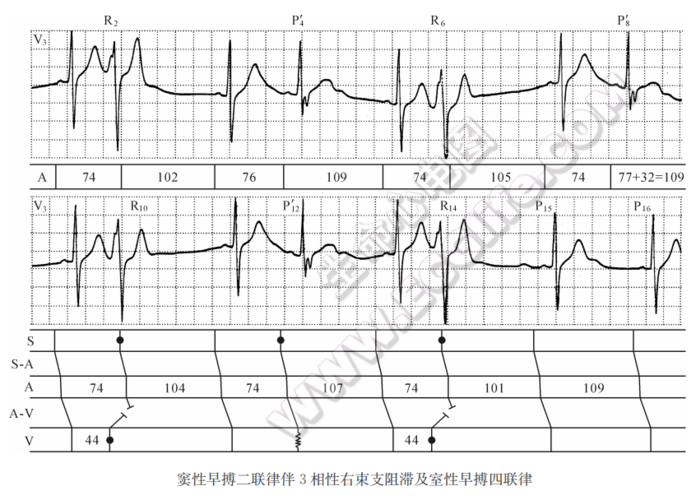

窦性早搏二联律伴3相性右束支阻滞及室性早搏四联律心电图精解